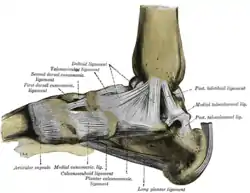

Ligaments of the medial aspect of the foot. (Calcaneocuboid labeled at bottom center.) | |

Ligaments

There are five ligaments connecting the calcaneus and the cuboid bone, forming parts of the articular capsule:

- the dorsal calcaneocuboid ligament.[2]

- part of the bifurcated ligament.[2]

- the long plantar ligament.[2]

- and the plantar calcaneocuboid ligament.[2]